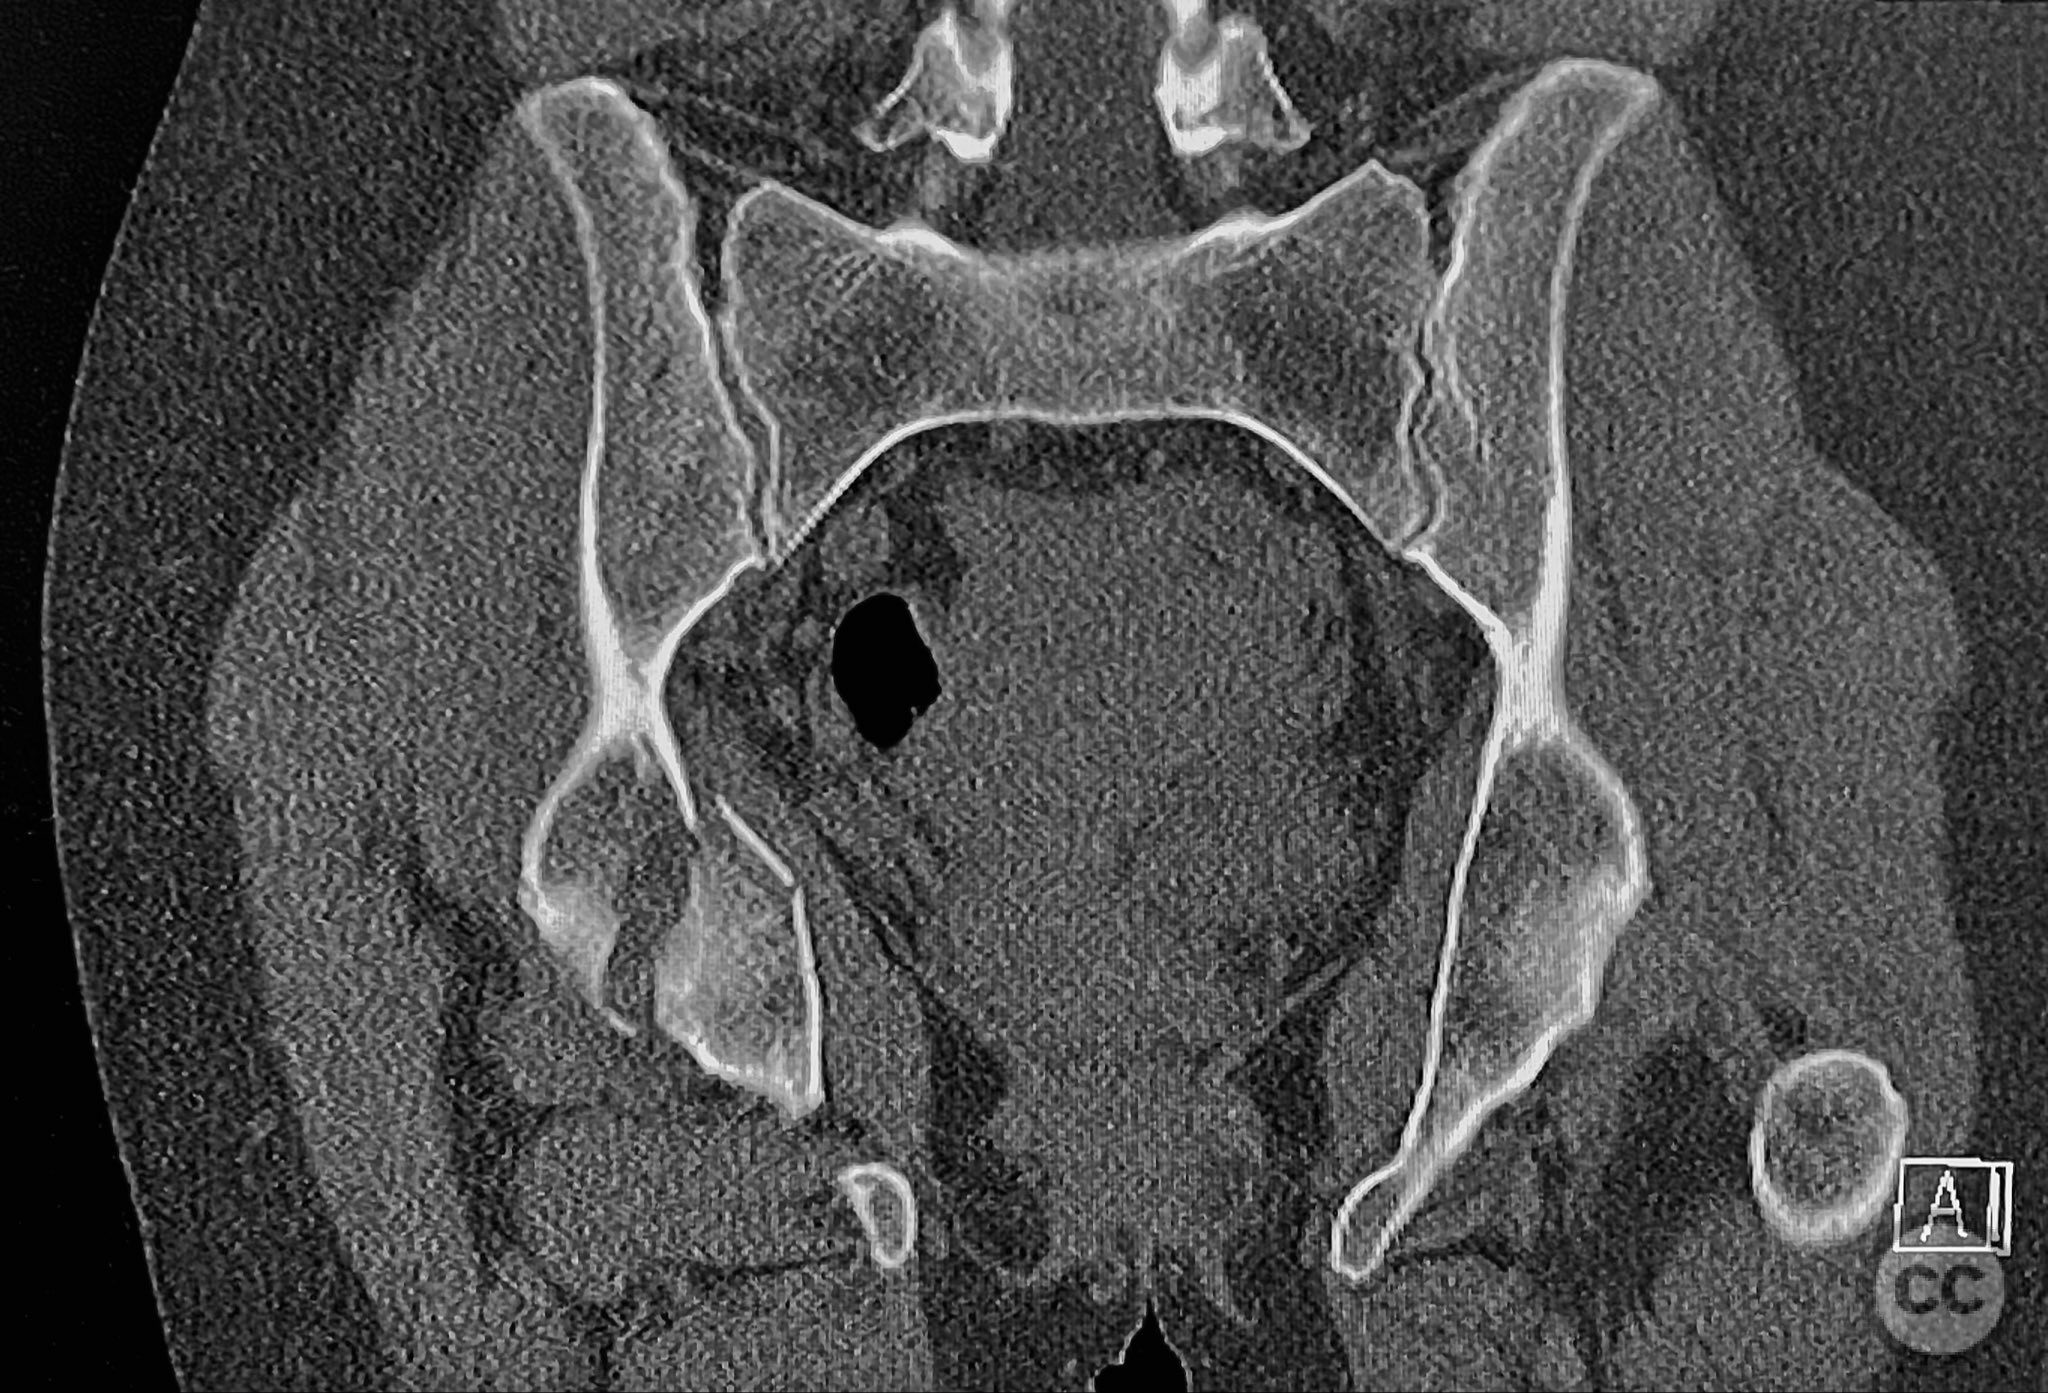

Clinical and radiological findings:  The patient sustained an acetabular fracture with a rare posterior medial dome impaction fragment, as demonstrated on AP pelvic radiographs obtained in skeletal traction. Surface renderings and axial CT images revealed multiple incomplete fracture lines, including a rhomboid-shaped cortical fragment adjacent and proximal to the anterior column/wall fragment. Coronal and sagittal reconstructions further delineated the impacted articular fragment and its relationship to the surrounding acetabular dome. The fracture pattern is classified as AO/OTA 62B3 (associated both-column fracture with dome impaction).

Planning remarks:  The preoperative plan involved an ilioinguinal approach to the acetabulum, utilizing the intrapelvic interval for initial reduction and stabilization of the posterior column with a contoured intrapelvic plate. Sequential reduction of the anterior column and direct management of the impacted dome fragment were planned, facilitated by temporary removal of the rhomboid cortical fragment.